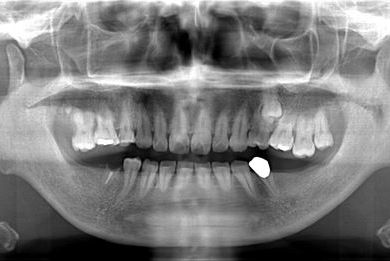

インプラントの症例写真 IMPLANT

インプラント治療+セラミック治療

| 主訴 | 前歯や、下の奥など、何本か気になる歯がある。 | ||||||||||||||||||||||||||||||||

| 治療方針 | インプラント治療により、機能的・審美的回復を行う。 | ||||||||||||||||||||||||||||||||

| 治療内容 | インプラント2本、メタルボンドセラミッククラウン4本、ジルコニアフレームオールセラミッククラウン1本(オールセラミック用土台1本) | ||||||||||||||||||||||||||||||||